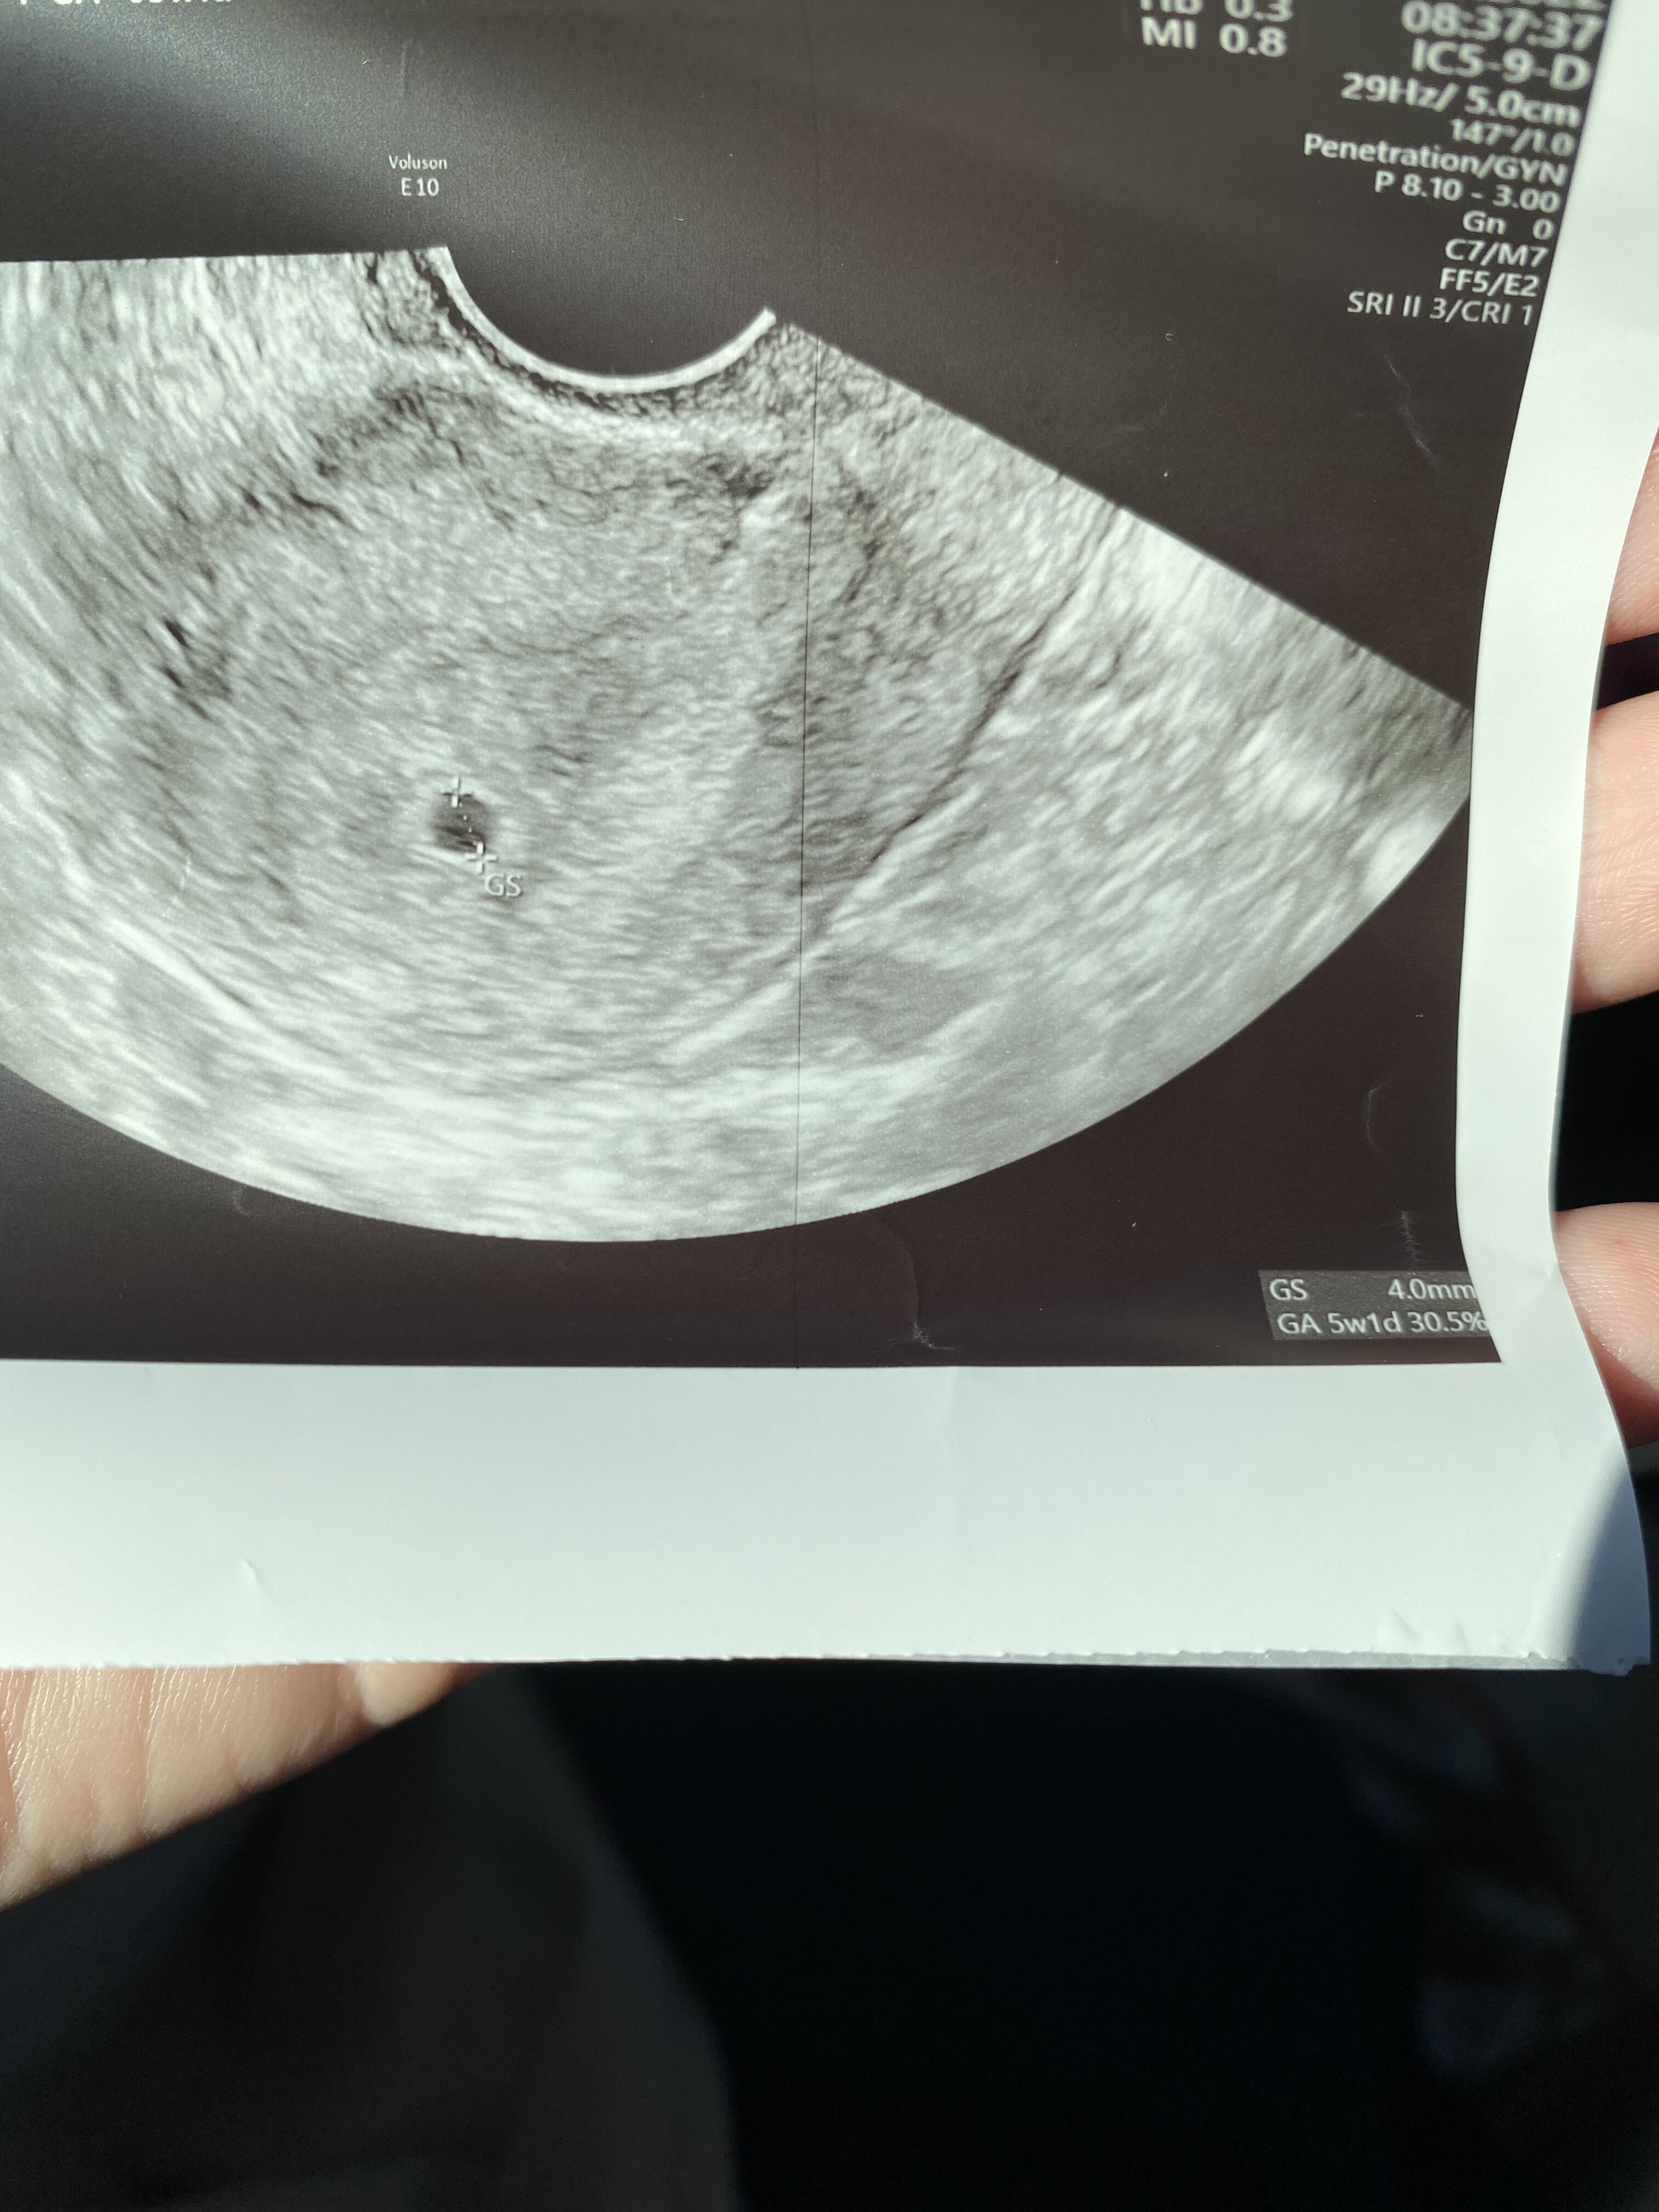

TakDziewczyny podpowiedzcie mo prosze, bo już zgłupiałam. Czy na zdjęciu usg tam w prawym dolnym rogu gdzie jest podany wiek ciąży pod wymiarem pęcherzyka, to jest wiek ciąży obliczony przez aparat usg na podstawie wielkości pęcherzyka ?

Dla mnie pęcherzyk jest widoczny, na upartego nawet echo zarodka może być widać.Dziewczyny 7 wrześni byłam na pierwszym usg. W macicy widoczny pęcherzyk ciążowy o wym 9,98 x 7.94. Brak pęcherzyka żółtkowego. Następne usg 19 września. Ostatnia miesiączka 25 lipca. Przeważnie cykle 31-33 dni. Myślicie, że jest szansa że pijawi się jeszcze pęcgerzyk żółtkowy i zarodek. Na usg widać w pęcherzyku jakąś dziwna smuge. Beta w dniu usg ponad 4600